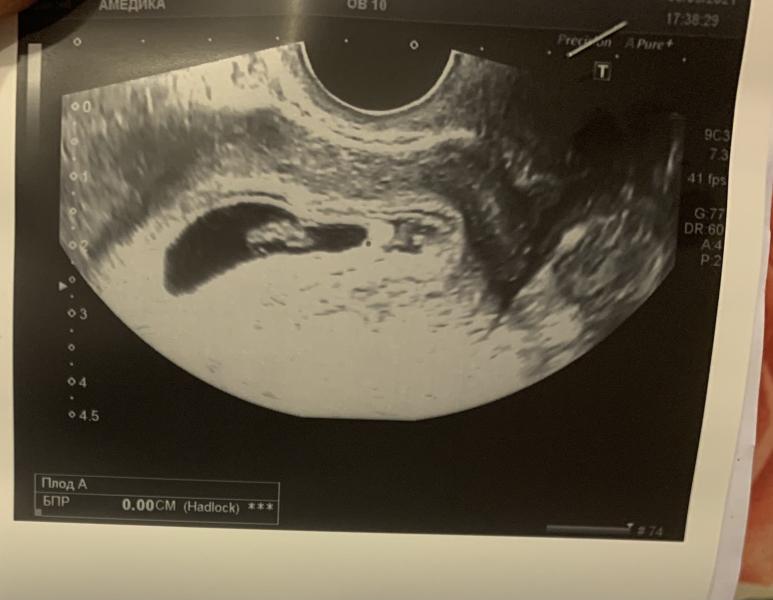

Вот мое узи 6 недель 6 дней. Как думаете кто будет???🥰 💙or💝???

По этому методу, если вагинально, то мальчик 😁